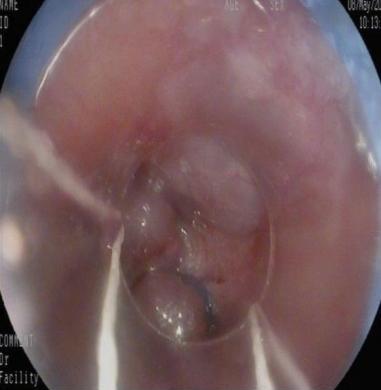

• 获得性免疫缺陷综合征合并马尔尼菲篮状菌导致肠道感染的内镜下表现(附6例报告)

2026, 32(3):84-88. DOI: 10.12235/E20250461

摘要 (32) HTML (27) PDF 3.50 M (26) 评论 (0) 收藏

摘要:目的 探讨获得性免疫缺陷综合征(AIDS)合并马尔尼菲篮状菌(TM)感染导致肠道感染的内镜下特征。方法 回顾性分析2022年11月-2024年10月于该院确诊为AIDS合并TM感染导致肠道感染的6例患者的临床资料。包括:临床症状、实验室检查、影像学检查、内镜检查和病理检查等。结果 6例患者中,男5例,女1例;发病年龄26~67岁;AIDS合并TM感染导致肠道感染患者的临床表现为:腹泻、腹痛、腹胀和恶心呕吐。其中,2例有消化道出血表现。实验室检查:6例患者外周血白细胞计数为(1.37~4.49)×109/L,血红蛋白计数为(67~99)g/L;CD4+T淋巴细胞为(1~52)个/μL,CD8+ T淋巴细胞为(61~321)个/μL,CD4+T淋巴细胞/CD8+T淋巴细胞比值为(0.01~0.18)。6例患者均行HIV RNA检测。其中,5例HIV RNA阳性。血培养:可见丝状真菌,报告显示为TM。影像学检查:6例患者CT结果可见肠系膜及腹膜后多发淋巴结肿大。内镜检查:6例患者内镜下均可见肠道病变。其中,十二指肠糜烂溃疡2例,结肠多发糜烂溃疡4例。病理检查:6例患者幽门螺杆菌(Hp)结果均为阴性,黏膜下可见成簇的小球形真菌孢子,符合TM感染;特殊染色:PAS(+),六胺银染色(+)。结论 当AIDS晚期患者出现消化道症状时,应警惕TM感染,病变部位常见于全结肠和直肠,亦可累及十二指肠,内镜下表现多为溃疡、糜烂和隆起性病变,形态表现无特异性;及时行胃肠镜检查、病理活检、特殊染色和免疫组化是确诊的关键。